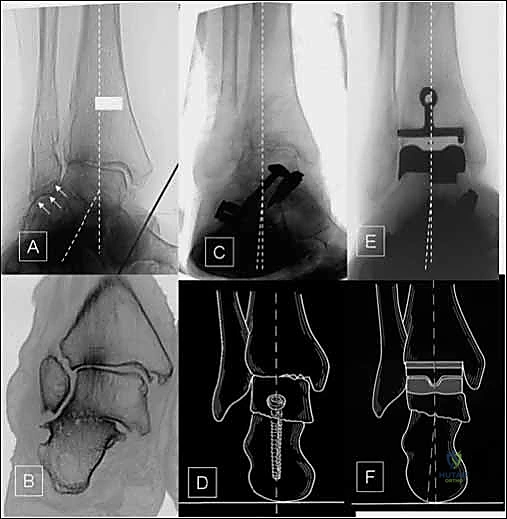

- الأشعة السينية (X-rays) بوضعية الوقوف: وهي الأداة الذهبية للتشخيص. صور الأشعة والوزن محمل على القدم (Weight-bearing X-rays) تظهر بدقة مدى تآكل الغضروف (ضيق المسافة المفصلية)، وجود نتوءات عظمية (Osteophytes)، وأي انحراف في المحور الميكانيكي للساق.

- الأشعة المقطعية (CT Scan): نلجأ إليها لفهم البنية العظمية ثلاثية الأبعاد بشكل أفضل، خاصة في حالات التشوهات المعقدة أو التخطيط الدقيق للقصات العظمية قبل الجراحة.

1. نظام سالتو لمفصل الكاحل الكلي (Salto Total Ankle Prosthesis - Mobile Bearing)

مفصل سالتو الأصلي هو ثمرة أبحاث أوروبية مكثفة. تم تطويره بين عامي 1994 و 1996، وبدأ استخدامه السريري بنجاح باهر في يناير 1997.

* التصميم الميكانيكي: يُعرف بأنه نظام ذو "مكون متحرك" (Mobile-bearing). يتكون من ثلاثة أجزاء رئيسية:

1. مكون معدني يثبت في أسفل عظمة الساق (Tibia).

2. مكون معدني يثبت في أعلى عظمة الكاحل (Talus).

3. قطعة بلاستيكية من البولي إيثيلين عالي الكثافة (Polyethylene insert): هذه القطعة ليست ثابتة، بل تنزلق بحرية بين المكونين المعدنيين.

* الميزة الكبرى: هذا التصميم يسمح بـ "التموضع الذاتي" (Self-alignment). أثناء الحركة، تتحرك القطعة البلاستيكية لتتكيف مع القوى الميكانيكية، مما يقلل من الضغط الواقع على واجهة التثبيت بين المعدن والعظم، ويحاكي حركة الكاحل المعقدة بشكل رائع.

* التثبيت: هو مفصل "غير إسمنتي". يتم تغطية الأسطح المعدنية الملامسة للعظم بطبقة مسامية من التيتانيوم وهيدروكسي أباتيت (Hydroxyapatite). هذه الطبقة تشجع العظم الطبيعي للمريض على النمو داخل مسام المفصل (Bone Ingrowth)، مما يوفر تثبيتاً بيولوجياً صلباً يدوم لسنوات طويلة.

2. نظام سالتو تالاريس (Salto-Talaris Prosthesis - Fixed Bearing)

بناءً على النجاح الهائل لنظام سالتو، تم تطوير نظام سالتو تالاريس لتلبية متطلبات مدارس جراحية مختلفة (خاصة في الولايات المتحدة).

* التصميم الميكانيكي: يشارك هذا النظام نفس الهندسة التشريحية الممتازة للمكونات المعدنية لنظام سالتو، ولكن مع اختلاف جوهري واحد: المكون البلاستيكي (البولي إيثيلين) هنا ثابت (Fixed-bearing) ويتم قفله بإحكام داخل المكون المعدني العلوي (الظنبوبي).

* الفلسفة وراء التصميم: أثبتت الأبحاث وخبرة الجراحين، بما في ذلك الأستاذ الدكتور محمد هطيف، أنه إذا تم إجراء القصات العظمية أثناء الجراحة بدقة متناهية تتوافق مع التشريح الطبيعي، فإن الحاجة إلى حركة واسعة للمكون البلاستيكي تقل بشكل كبير.

* الميزة الكبرى: نظام سالتو تالاريس يوفر استقراراً